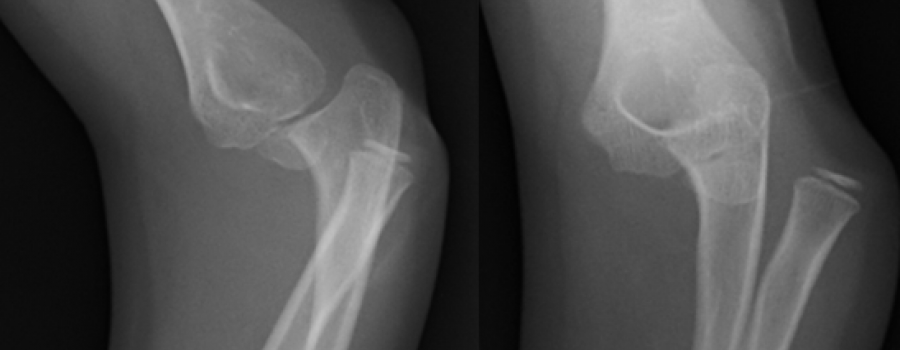

Große stielförmige Exostose

Patient 14 Jahre alt männlich. Kommt wegen einer Distorsion des linken Knies in die Notfallambulanz.